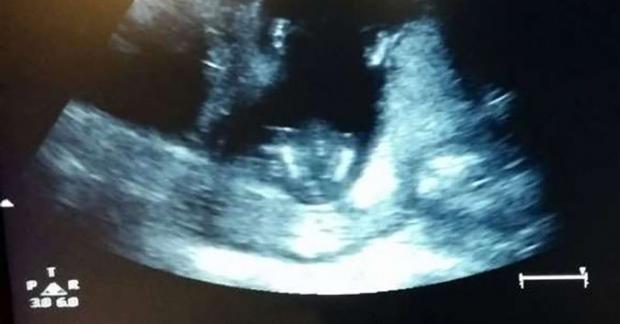

Các bà mẹ thường yêu thích việc “giao lưu” với thai nhi trong bụng, mặc dù không biết em bé có thể nghe hiểu được hay không vậy nhưng đối với họ có lẽ cảm giác này vẫn thật tuyệt vời. Một cặp vợ chồng đi siêu âm và phát hiện em bé mới 14 tuần tuổi trong bụng có phản ứng bất ngờ.

Bác sĩ đang chuẩn bị tiến hành siêu âm cho bà mẹ

Cặp vợ chồng này cùng hát một ca khúc “Nếu bạn cảm thấy vui và cảm nhận được điều đó hãy vỗ tay”, thật bất ngờ em bé trong bụng mẹ đã vỗ tay theo nhịp bài hát.